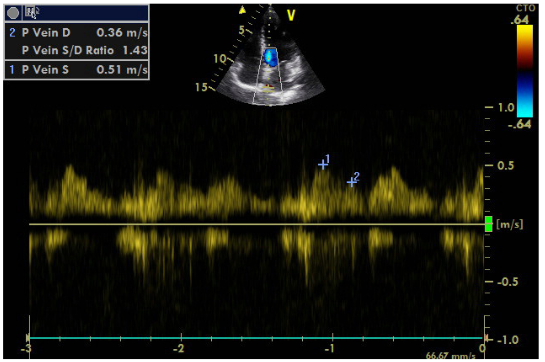

An additional element is the localization of the stenosis in the initial part of renal vessel, as opposed to FMD that commonly affects the middle and peripheral portions. The sudden deterioration of renal function within a short period of time also advocates for atherosclerosis as the FMD has a slower course. It is noted that atherosclerosis may lead to complete abstraction/thrombosis over time, rarely occurring FMD. Finally, the immunological test performed to rule out vasculitis was negative. Renal arteriography indicated a 99% stenosis to the left and the patient underwent a successful stent implantation. After angioplasty, blood pressure returned to normal and the patient did not receive any medication. It is worth noting that despite the presence of stage III hypertension and the underlying disease, the patient did not show signs of diastolic dysfunction in the Doppler (Figures 8–10), nor any signs of hypertrophic left ventricle in ECG.  Not a patient with long-standing uncontrolled hypertension. Moreover, to stress echocardiography with doboutamine there were no wall motion abnormalities, while coronary flow reserve was normal (CFR LAD=2.2) (Figure 11A & 11B).

Figure  9 Doppler  of pulmonary vein flow.